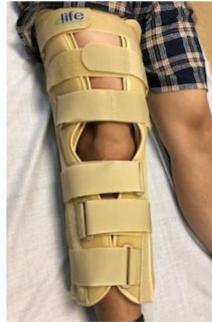

| Knee Immobilizer | Lower Limb | Immediate after knee injuries (instability, patellar fractures, haemarthrosis); post knee surgery | Apply with wider end on upper thigh; ensure opening is on the patella; apply tightly from up downwards. | , ![]() |